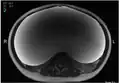

MRI giant serous cystadenoma ovary